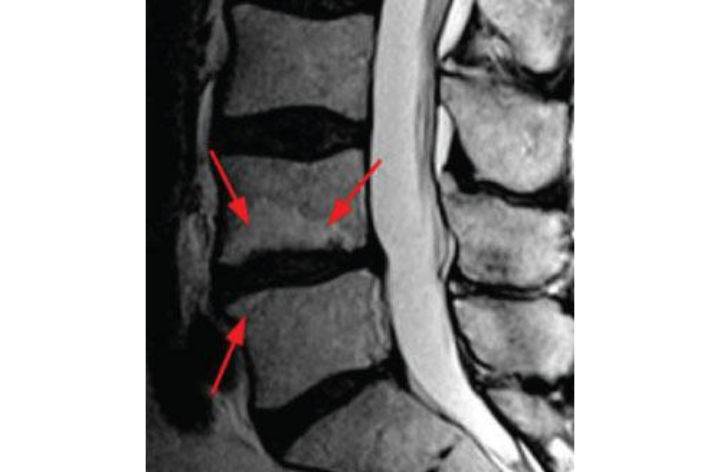

Кт признаки остеохондроза